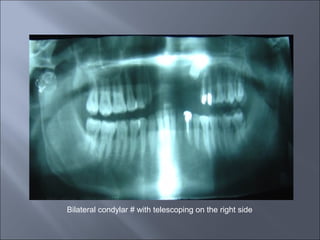

Bilateral condylar # with telescoping on the right side

Bilateral condylar #with telescoping on the right side